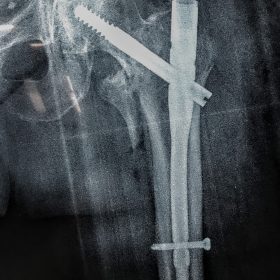

Υποτροχαντήριο :Εξωαρθρικό κάταγμα κάτω από τον ελάσσονα τροχαντήρα του μηριαίου οστού. Αντιμετωπίζεται χειρουργικά με ενδομυελική ήλωση τύπου Long γ-Nail. Δύο τομές 3 εκατοστών και 1 εκατοστού αντιστοίχως για την εισαγωγή και το κλείδωμα του ήλου μέσα στο οστό. Η μέθοδος είναι κλειστή,σχεδόν αναίμακτη,διάρκειας 60 λεπτών,με τη βοήθεια C-ARM (τηλεόρασης). Στον ασθενή παρέχεται οπτικό υλικό (όλα τα χειρουργικά στάδια) σε CD ή Στικάκι,λόγω της δυνατότητας καταγραφής του χειρουργείου από το C-ARM Ο ασθενής περπατάει άμεσα μετεγχειρητικά στις 5 ώρες μετά την επέμβαση και εξέρχεται από το νοσοκομείο σε 1 -2 ημέρες.